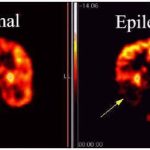

Si ritiene che la suscettibilità poligenica sia un fattore importante nella patogenesi della SM e l’ereditabilità della SM è stata stimata in 0,64 (IC 95% 0,36-0,76). Le analisi post genome-wide association studies (GWAS) forniscono un’opportunità per questo vuoto. Ad esempio, gli studi di associazione proteome-wide (PWAS) sviluppati di recente stabiliscono associazioni tra l’abbondanza del proteoma e il fenotipo della malattia utilizzando loci di tratto quantitativo proteico (pQTL) per spiegare gli effetti delle architetture genetiche in termini di proteine regolate da cis a valle. ……Per determinare se i geni di suscettibilità identificati dall’analisi integrativa fossero espressi in modo diverso nel cervello post-mortem della SM, è necessario esplorare successivamente l’espressione dei geni di rischio da due dimensioni, distribuzione (sostanza bianca e grigia) e grado della lesione (lesione e aspetto normale tessuto). La SM era precedentemente considerata una malattia demielinizzante che coinvolge la sostanza bianca, recentemente le convulsioni e il deterioramento cognitivo sono due sintomi della SM che possono essere causati da lesioni infiammatorie che danneggiano la materia grigia ricca di neuriti e corpi cellulari neuronali. Pertanto, oltre alla sostanza bianca, le lesioni corticali che hanno un ruolo importante nella fisiopatologia della SM devono essere esplorate.